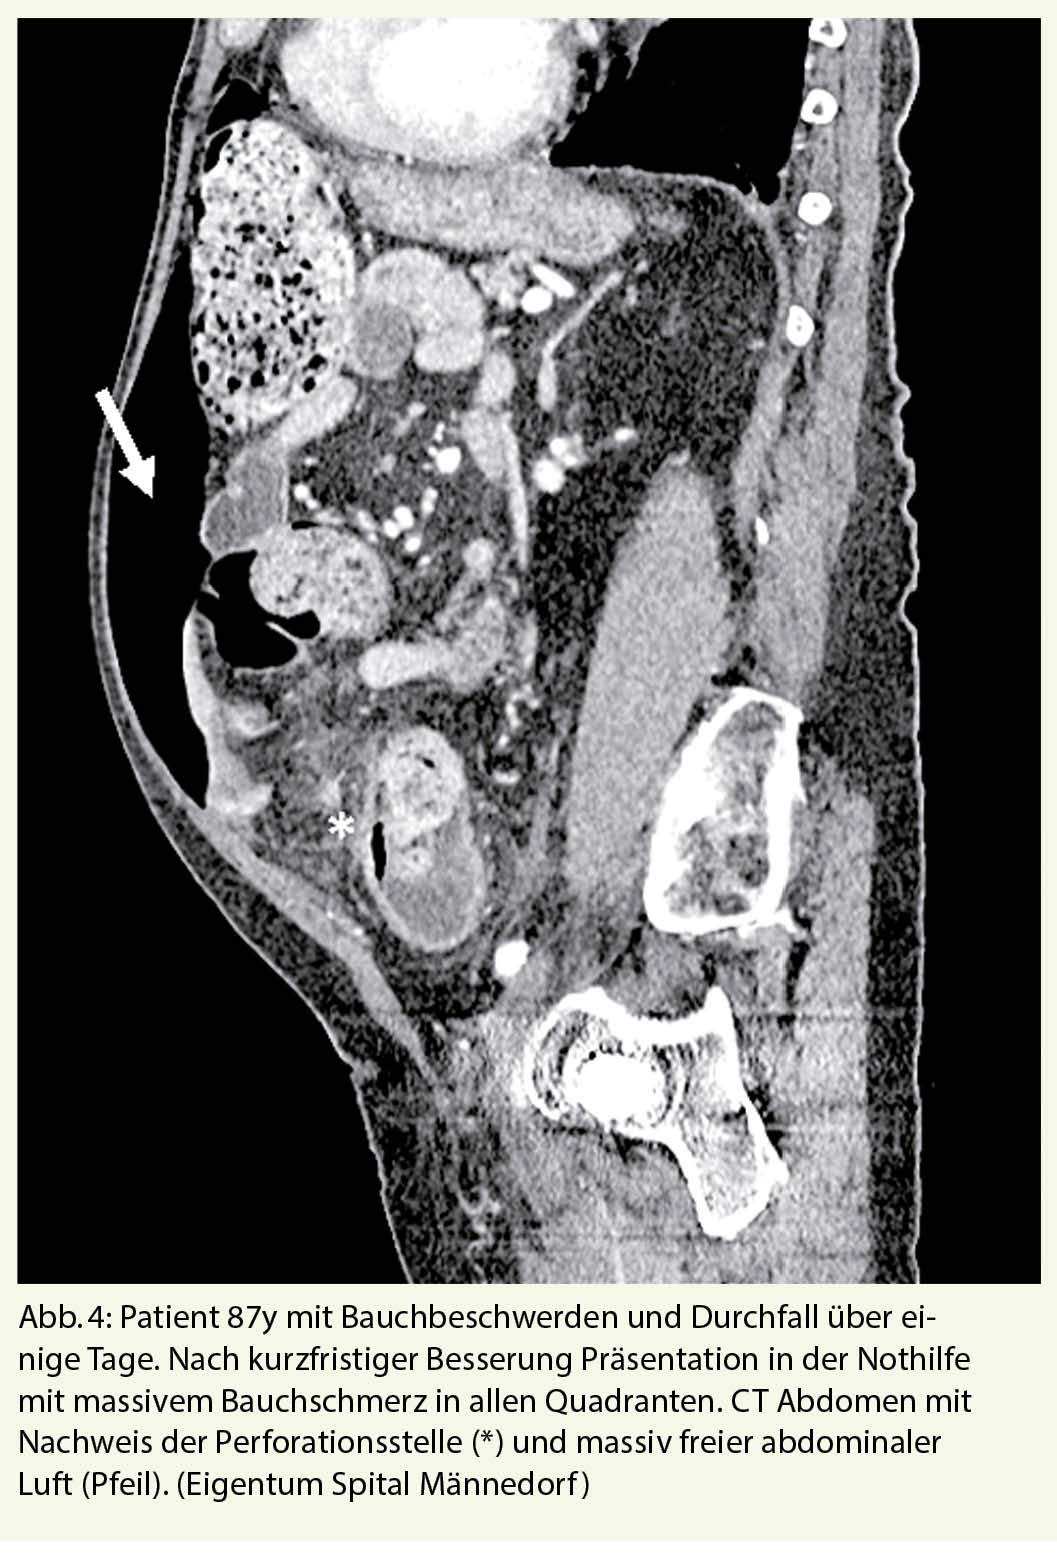

Akute Divertikulitis

Die akute Divertikulitis des Dickdarms ist eine der häufigsten Erkrankungen, die zu einer Einweisung in den Notfall führen. Bei mehr als 50 % der über 65-Jährigen liegt eine Divertikulose vor, aus der in 10-25% eine akute Divertikulitis entstehen kann (13, 14). Auch bei einer perforierten Divertikulitis können typische Schmerzen im linken Unterbauch mit Abwehrspannung fehlen, so dass auch hier nur eine Computertomographie des Abdomens zur Klärung der Situation beiträgt. Nicht selten präsentieren sich ältere, immungeschwächte Patienten primär mit einer frei perforierten Sigmadivertikulitis, die mit einer massiven eitrigen Peritonitis und entsprechend hoher perioperativer Letalität einhergehen kann (Abb. 4)